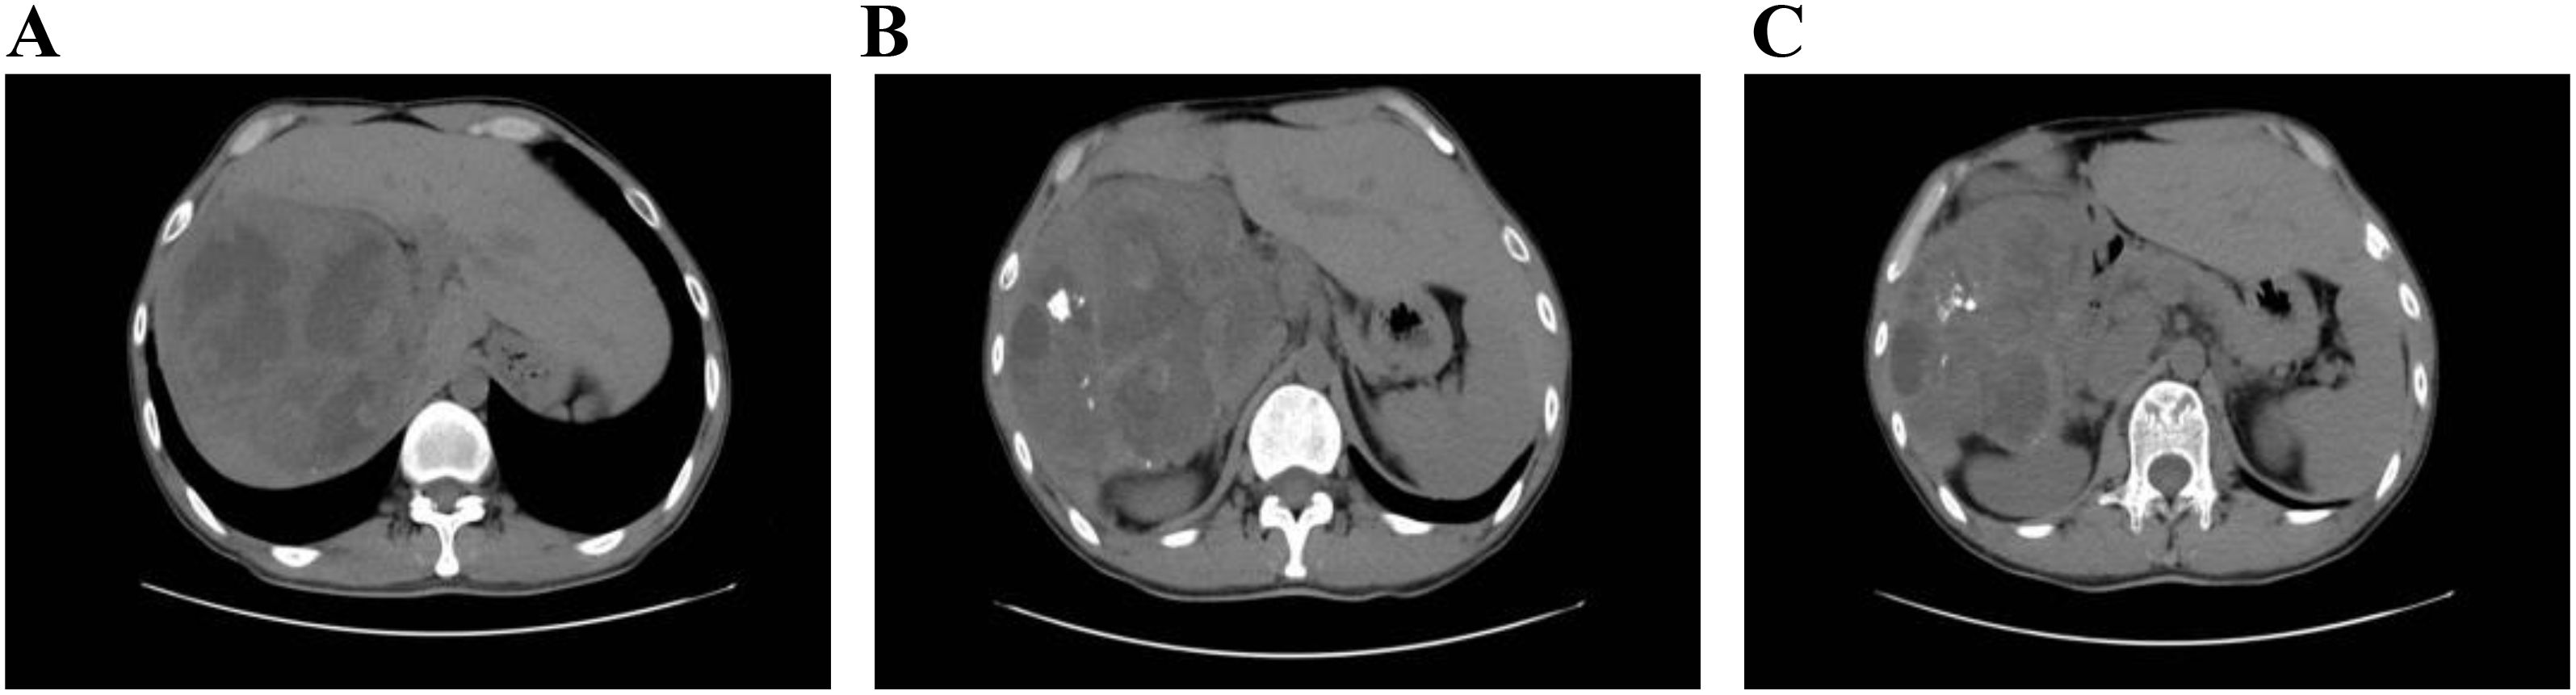

Introduction: Intrahepatic papillary neoplasm of the bile duct (IPNB) with invasive carcinoma is a rare cholangiocarcinoma with most frequent site of origin being intrahepatic bile ducts. Given its rarity and nonspecific clinical presentations, accurate diagnosis plagues clinicians to improve patient outcomes. Case presentation: We present a case of a 31-year-old male who initially exhibited fever. Routine ultrasonography and computed tomography (CT) revealed a large mass in the right liver lobe, suggesting a high likelihood of an infectious lesion. However, multidisciplinary discussion offered a variety of possible scenarios. The patient subsequently underwent an extend right hepatectomy (ERH), and histopathological examination suggested a intrahepatic IPNB with invasive adenocarcinoma. Clinical discussion: The diagnosis and management of IPNB remain challenging, particularly in patients who present with atypical clinical symptoms and lack significant abnormalities in laboratory tests. Early imaging plays a critical role in guiding the diagnostic process. However, a comprehensive diagnostic speculations, clinical expertise, and even invasive detections are essential for establishing a definitive diagnosis and determining the appropriate treatment strategy. Given the potential to invasive carcinoma, early detection and resection are vital to improve prognosis.